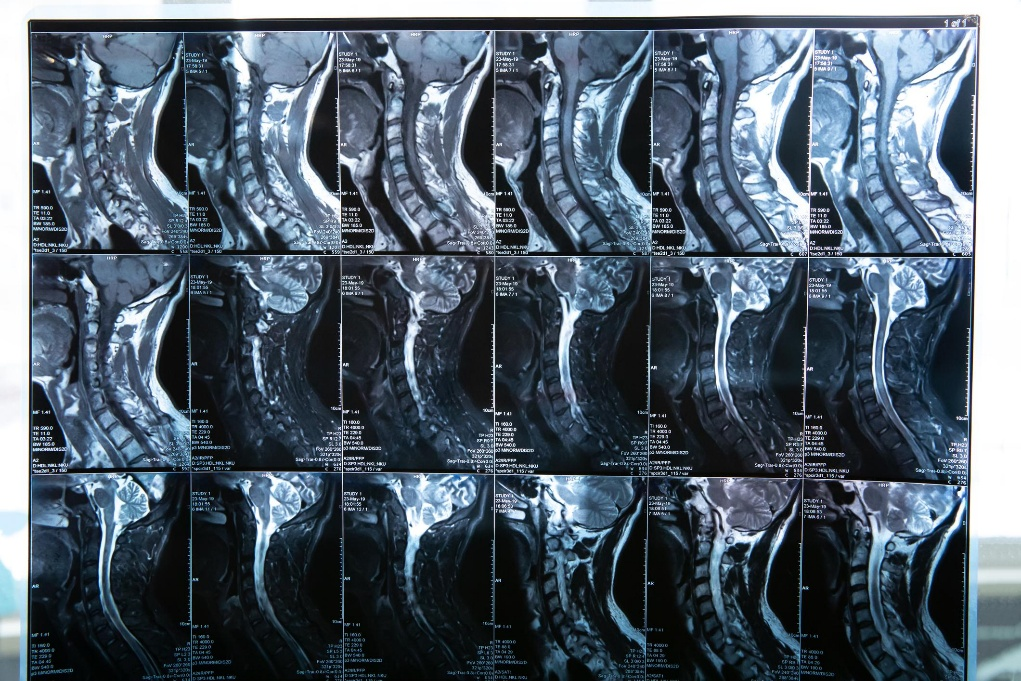

The Elevation Health Approach: Objective Data, Measurable Outcomes When it comes to spine and injury care—especially for patients who have been injured in a car accident—one of the biggest frustrations is uncertainty. Patients are often told they should feel better, that healing “takes time,” or that pain levels are subjective. At Elevation Health, the approach […]